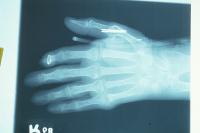

Preop films.

Click for larger image